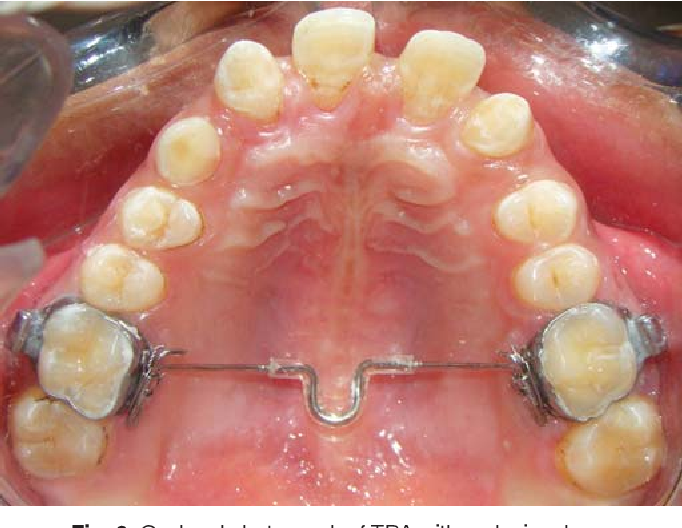

The morphology of the pulp chamber in primary molars can be evaluated using spiral computed tomography (SCT) (Selvakumar et al., 2014). SCT can provide information on the distance between the central fissure and furcation, the distance between the central fissure and the floor of the pulp chamber, the height of the pulp chamber, and the distance between the floor of the pulp chamber and the furcation (Selvakumar et al., 2014).